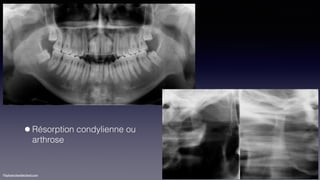

•Résorption condylienne ou

arthrose